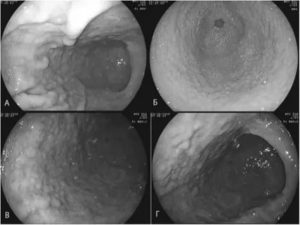

2. При проведении фиброгастродуоденоскопии визуализируется один из опорных критериев диагноза так называемая бархатная слизистая и различной степени распространенности воспалительные изменения.

5. При проведении хроматографии отмечается своеобразная мозаичность слизистой оболочки, зоны с цилиндрическим эпителием интенсивно окрашиваются, в отличие от нормальной слизистой пищеводной трубки.